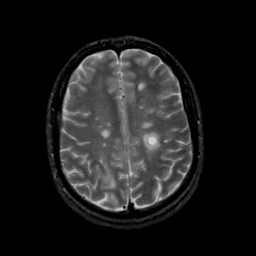

MR Study #21, November 3, 1991 -- Slice #35